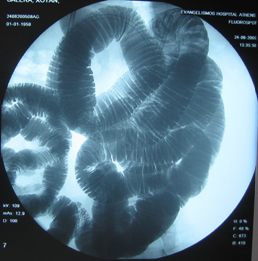

Στους ίδιους ασθενείς η εντερόκλυση μπορεί να αναδείξει ανάλογα ευρήματα με την ενδοσκοπική κάψουλα (εικόνες 36-43) ή να είναι φυσιολογική (εικόνες 44-48).

36  37

Εικόνες 36, 37. Ο ίδιος ασθενής με τις εικόνες 15, 16. Εικόνα πλακόστρωτου με στένωση και παρουσία        βαθιάς εξέλκωσης του βλεννογόνου

38  39